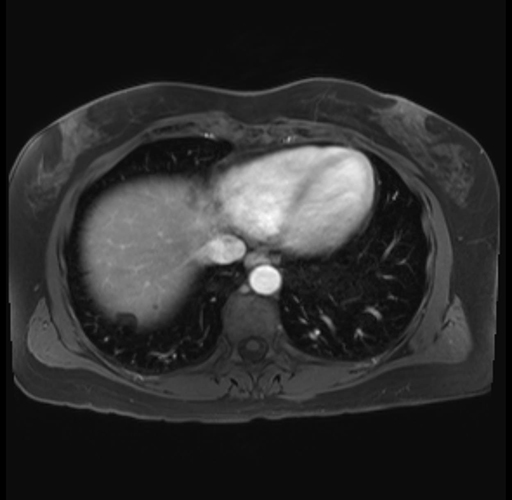

Imaging Analysis

Look through the patient's CT scan to identify any areas of concern for the necessary procedure.

Based on your CT findings, which issue(s) are present and would give reason for "planned slowing down moment(s)" in this case?